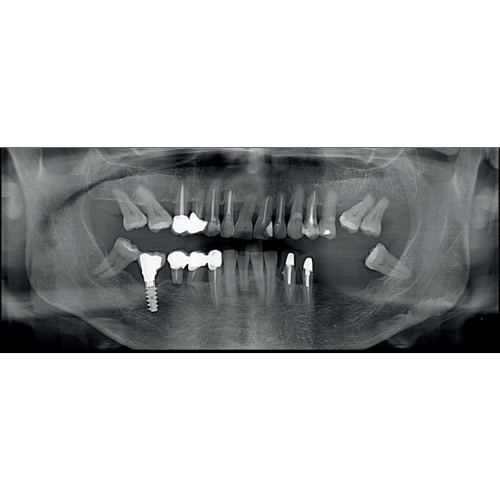

X-MIND® optima 3D represents the perfect combination of advanced hardware technology, enclosed in a lightweight and compact design and next-generation software, RealGuide™ 5.4, bringing the benefits of Artificial Intelligence into every step of patient care, from a precise diagnosis to more effective treatments and patient communication.

- 2D and 3D Imaging

- Panoramic

- Pedo Friendly